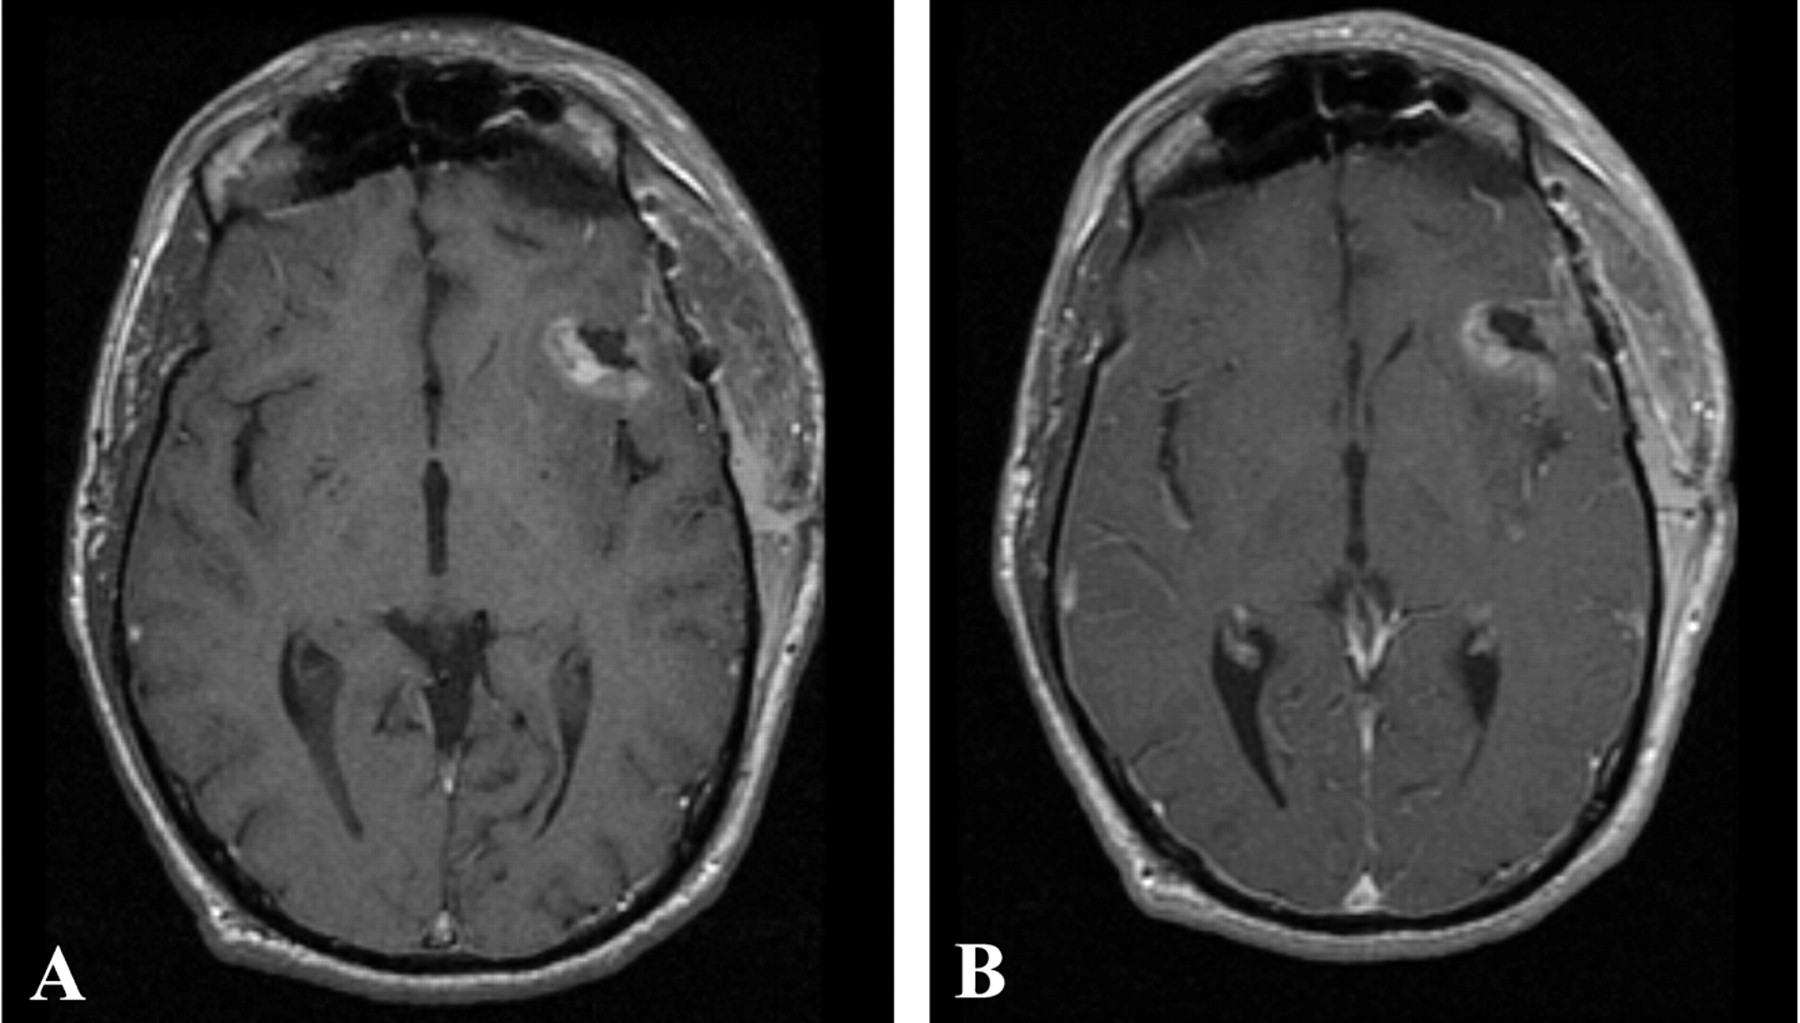

Both patients underwent IMRI-guided resection of their tumors. Preoperative MR imaging demonstrated the targeted lesion. Intraoperative MR without gadolinium, following the prior administration of ferumoxtran-10, easily provided images that demonstrated the lesions seen on preoperative MR images obtained in both patient 1 (Fig 1) and patient 2 (Fig 2). In one operation, post-resection imaging revealed a persistently enhancing area that was then resected (Fig 3). Even in the low-field-strength IMRI system, ferumoxtran-10 provided adequate imaging of the lesions in both of these patients. Postoperative MR images obtained in both patients had no significant enhancement with gadolinium, which suggests resection of the enhancing tumor bulk (Figs 4 and 5). Both postoperative MRIs show high T1 signal intensity in the wall of the resection cavity. The walls of the cavities, however, do not appear to enhance significantly with gadolinium. Figure 5 also shows the resection cavity itself filled with T1 hyperintense material. The cause of this residual T1 hyperintensity, either from blood or ferumoxtran, is unclear. Iron staining of one patient’s lesion demonstrated iron accumulation within peritumoral reactive cells (Fig 6).

Postoperative T1-weighted MR imaging from patient 1 performed 72 hours after surgery, without (A) and with (B) gadolinium. No residual areas of significant gadolinium enhancement are seen.

Postoperative T1-weighted MR imaging from patient 2 performed 24 hours after surgery, without (A) and with (B) gadolinium. No significant gadolinium-enhancing areas are seen, although they may be masked by residual T1 signal intensity. These images demonstrate the difficulty with postoperative imaging in the face of blood products and hemostatic agents.